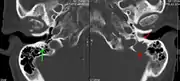

The diagnostic examination of a person with suspected multiple myeloma typically includes a skeletal survey. This is a series of X-rays of the skull, axial skeleton, and proximal long bones. Myeloma activity sometimes appears as "lytic lesions" (with local disappearance of normal bone due to resorption) or as "punched-out lesions" on the skull X-ray ("raindrop skull"). Lesions may also be sclerotic, which is seen as radiodense.[70] Overall, the radiodensity of myeloma is between −30 and 120 Hounsfield units (HU).[71] Magnetic resonance imaging is more sensitive than simple X-rays in the detection of lytic lesions, and may supersede a skeletal survey, especially when vertebral disease is suspected. Occasionally, a CT scan is performed to measure the size of soft-tissue plasmacytomas. Nuclear Medicine Bone scans are typically not of any additional value in the workup of people with myeloma (no new bone formation; lytic lesions not well visualized on nuclear bone scan).